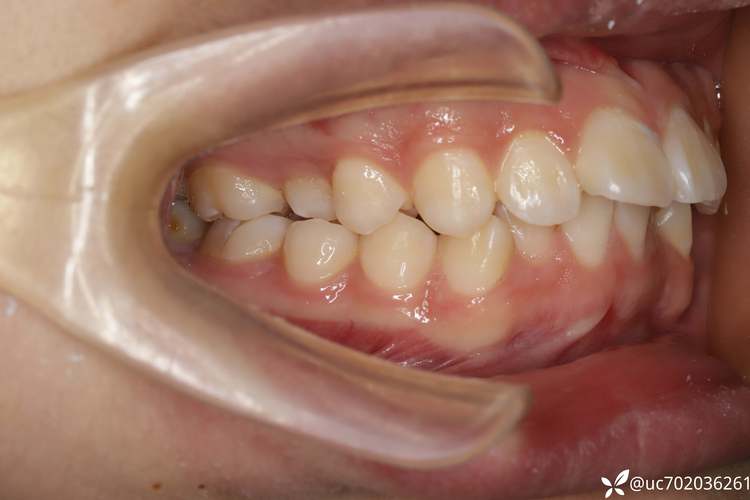

牙齿矫正的本质是利用生物力学原理,在牙槽骨中移动牙齿,最终达到“排列整齐、咬合稳定、面型协调”的目标,但并非所有牙齿都能顺利移动,当出现以下问题时,拔牙可能是必要选择:

- 牙量与骨量不调:这是最常见的原因,部分人的颌骨(牙床)空间不足以容纳所有牙齿,导致牙齿拥挤、错位,就像“小房子里住太多人”,只能通过“减少人口”(拔牙)为剩余牙齿腾出空间。

- 改善牙齿前突:对于“龅牙”(上颌前突)患者,单纯排齐牙齿无法改善突度,拔除部分前磨牙后,可通过内收前牙,减少牙弓长度,使嘴唇更贴合面型,改善侧貌美观。

- 调整咬合关系:深覆合(上牙过度覆盖下牙)、深覆盖(上牙过度前伸)等问题,有时需要拔牙后配合垂直向或水平向移动,打开咬合、建立稳定的咬合接触点。